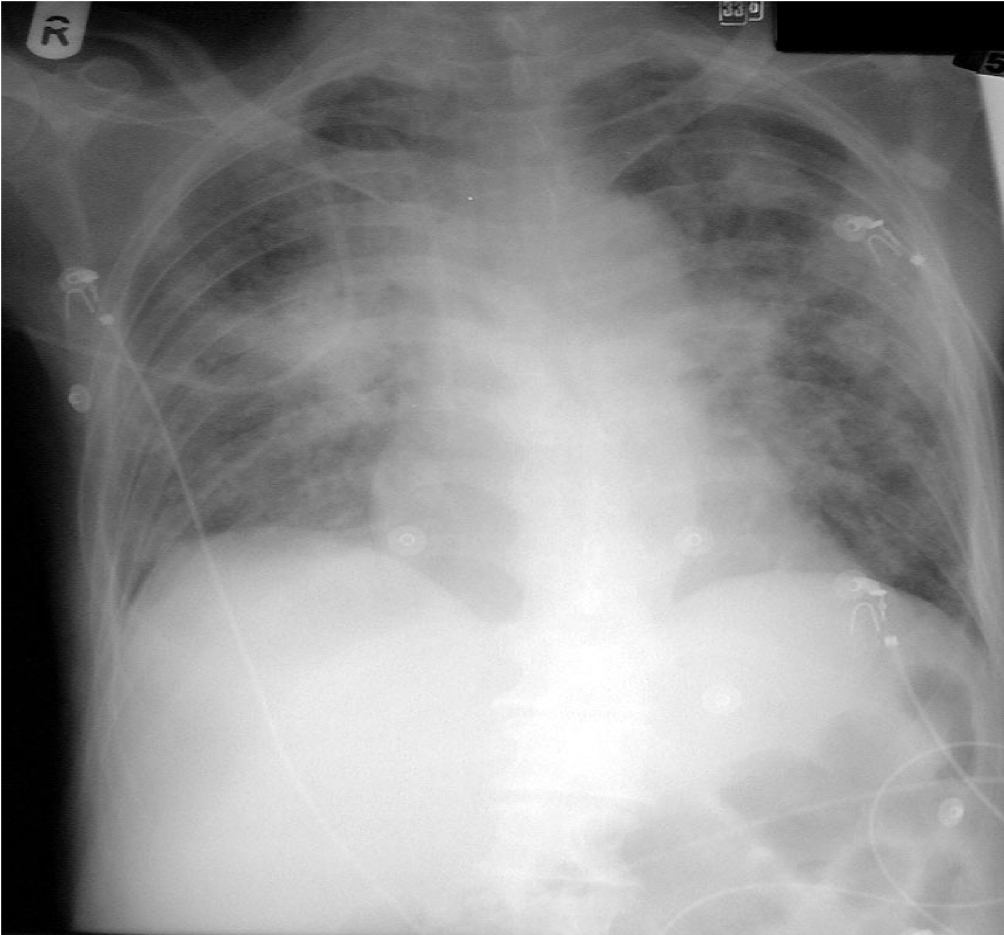

Fungal pneumonia in AML – CXR 24 hours later

Rapid dissemination